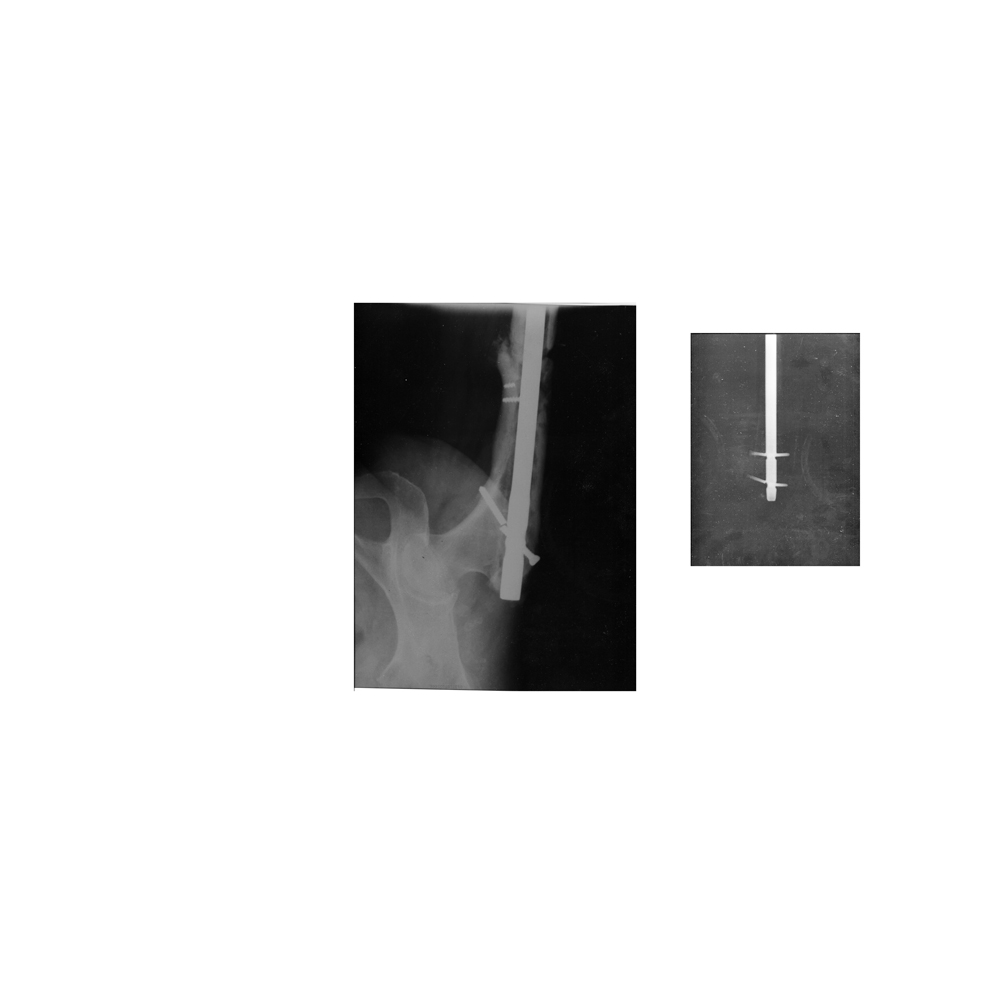

Отправитель: Людмила 09 Сентябрь 2015, 01:07

Пожалуйста, посмотрите снимок. Был проведен остеосинтез гвоздем. Гвоздь сломался. Сделали повторную операцию год назад. Перелом не сросся. Все блокирующие шурупы сломались. Что делать? Ждать, пока сломается очередной гвоздь? Если ли надежда на сращение? Спасибо заранее за ответы.